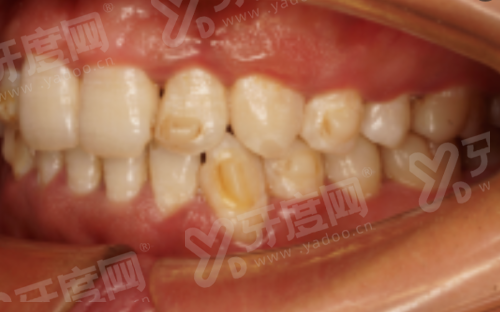

2. 针对性解决早期问题:针对乳牙期、替牙早期或中期孩子的牙弓狭窄、牙列不齐、颌骨发育不良(如凸嘴、地包天等面型问题),从根源改善颌骨和牙齿的协调性,减少后期复杂矫正需求。

1. 减少拔牙矫正几率:在孩子生长发育黄金期及时干预,通过非拔牙方案调整牙齿排列和颌骨位置,降低因牙齿拥挤、错位导致的拔牙需求,保护口腔自然结构。

2. 综合改善牙颌面健康:结合牙齿健康和颌面发育状况,从骨骼、牙齿、咬合三个维度优化,不仅解决牙齿不齐,还能改善面部轮廓,临床上已积累大量青少年儿童颌面管理成功病例,成效口碑较好。